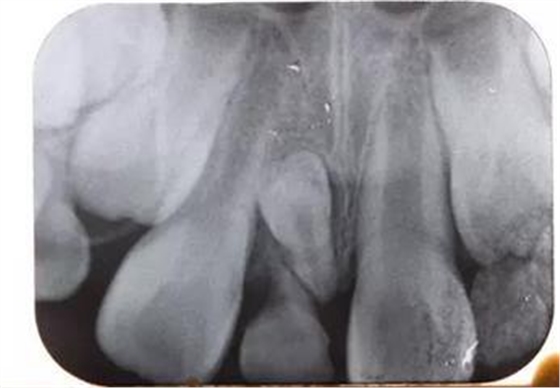

患兒,男,8歲半,混合牙列,11、12均已萌出,其間有一重度磨耗的51滯留,家長一直不知怎么回事,因為美觀問題,至當?shù)卦\所給予檢查,也許條件受限沒有X光牙片機的緣故,建議直接拔除51,然后矯正關(guān)閉間隙,家長不放心,來診,常規(guī)拍攝X線片發(fā)現(xiàn)乳牙滯留和間隙存在的原因是有一埋伏倒置多生牙的緣故,遂建議拔除滯留的51和埋伏的多生牙,然后擇期矯正。

X線片:51牙根基本吸收,下方顯示倒置多生牙。